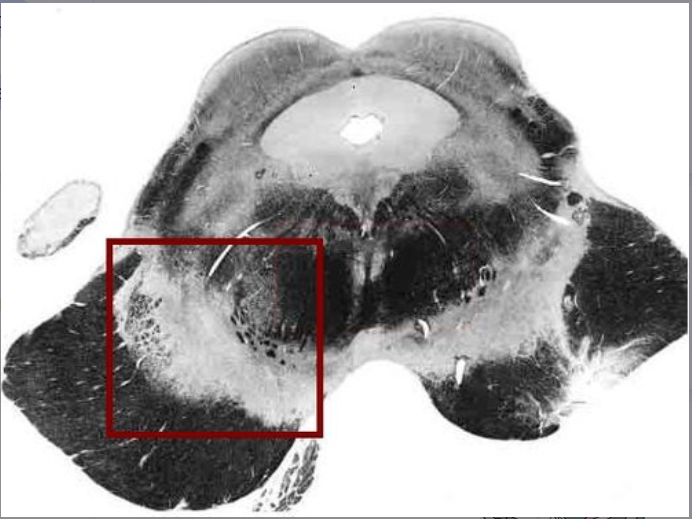

substantia nigra

located: midbrain

fxn: produces DOPAMINE (motor, cognition, behavior)

22

Q

A